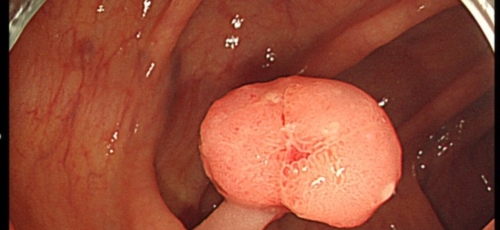

대장내시경

대장암을 초기에 발견해 내려면 대장내시경은 필수인데요 적어도 2년에 한 번 대장내시경을 받아 이상이 없나 확인해 봐야 합니다.CT촬영으로 혹이 보이거나 하는 경우가 있는데요, 사실 초기에 CT로 혹을 잡아내기는 매우 힘들다고 해요. 가장 정확한 건 의사가 눈으로 볼 수 있는 대장내시경이니 건강검진시 꼭 받으시기 바랍니다.

대장암 초기증상은 만성복통과 소화불량, 식욕저하, 변비, 설사 등의 다양한 형태로 나타날 수 있습니다. 하지만 초기에는 이렇다할 증상이 보이지 않아 건강검진을 하면서 우연히 발견되기도 합니다. 따라서 대장암을 조기에 발견하고 적기에 치료하기 위해서는 대장내시경 검사를 정기적으로 받는 방법뿐인데요 45세부터는 5년에 한 번씩 대장내시경 검사를 받도록 권장되고있는데, 만약 가족 중 대장암환자가 있거나 유전적 요인이 있는 경우에는 40세부터 정기적으로 검사받는것이 좋습니다.

특이 증상이 없더라도 국가에서 권장하고있는 건강검진 시기에 맞게 대장내시경을 하는 것이 좋습니다. 또한 이러한 증세가 나타난다면 빠른 시일 내에 진료를 통한 내시경 검사를 진행하여 정확한 진단과 그에 맞는 치료가 진행되어야 합니다. 꼭 대장암 초기증상이 아니더라도 대장질환이나 위장질환으로 인해 상황이 악화되어 나타날 수 있기때문에 그냥 넘기지않고 꼭 내원하여 적절한 치료를 받는것이 좋습니다.